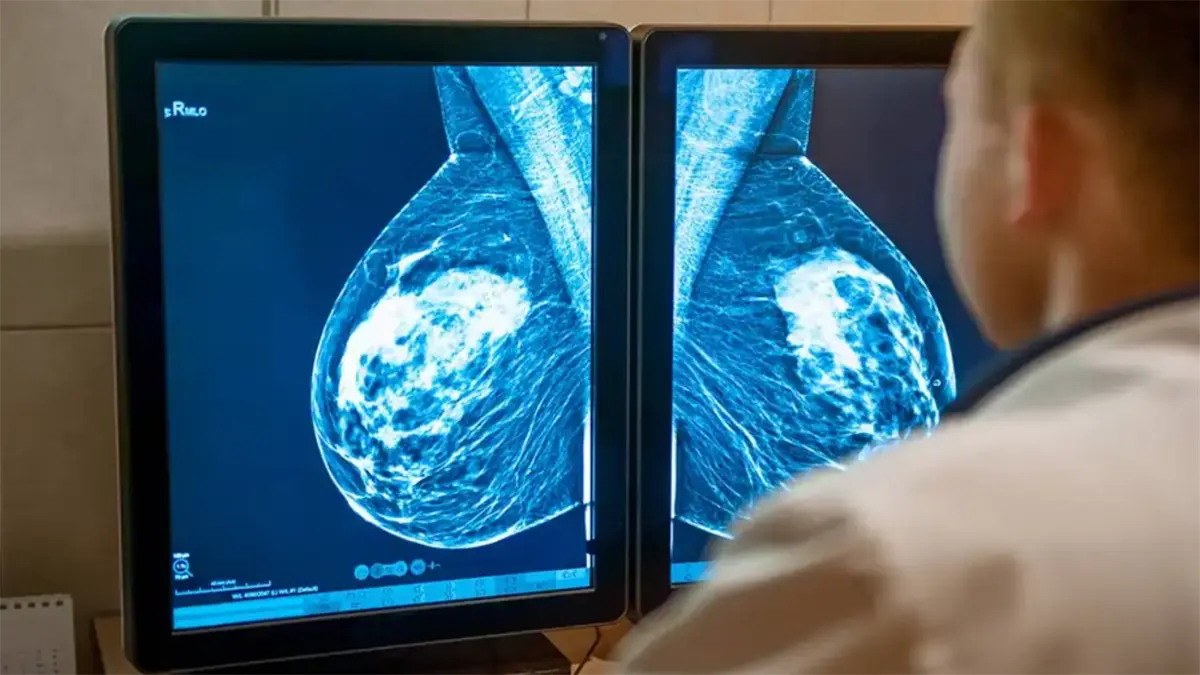

Sídney (Australia).- Un sistema de inteligencia artificial (IA) desarrollado en Australia podría transformar la forma en que se detecta y se previene el cáncer de mama, al identificar a mujeres con alto riesgo de desarrollar la enfermedad tras recibir una mamografía aparentemente normal, según un estudio publicado este miércoles.

La investigación, difundida en la revista The Lancet Digital Health, analiza una herramienta denominada BRAIx, que utiliza algoritmos de aprendizaje profundo para examinar imágenes mamográficas.

El sistema calcula una puntuación individual de riesgo de cáncer de mama en los años posteriores al examen, lo que permite anticipar posibles diagnósticos futuros.

El estudio, realizado por la Universidad de Melbourne, se basó en datos de más de 96.000 mujeres que participaron en el programa público BreastScreen en el estado de Victoria, al sur de Australia.

A partir de las mamografías, los investigadores calcularon el llamado índice de riesgo BRAIx.

Esta puntuación estima la probabilidad de desarrollar cáncer en el momento del cribado o en los cuatro años siguientes.

Los resultados mostraron que el sistema predice con gran precisión qué mujeres tienen mayor probabilidad de desarrollar la enfermedad tras un resultado negativo.

En particular, el 2 % de las mujeres con el índice de riesgo más alto presentaba cerca de un 9,7 % de probabilidad de recibir un diagnóstico de cáncer de mama en los cuatro años posteriores.

Esa cifra resulta comparable o incluso superior al riesgo de algunas portadoras de mutaciones genéticas asociadas a la enfermedad.